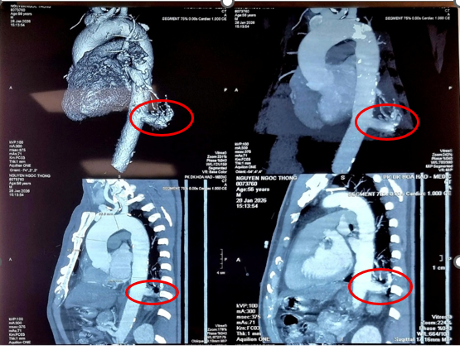

Tại Bệnh viện Bình Dân, ông được chẩn đoán mắc phổi biệt lập nội thùy với khối kích thước 23 mm × 26 mm. Đáng chú ý, động mạch nuôi khối này xuất phát trực tiếp từ động mạch chủ xuống với đường kính lên tới 17 mm - một kích thước rất lớn và đầy rủi ro nếu người bệnh không được điều trị.

Kết quả chụp MSCT ngực cho thấy phổi biệt lập nội thùy trong thùy dưới phổi trái, có nhánh mạch máu nuôi lớn xuất phát từ động mạch chủ ngực, rất nguy hiểm

ẢNH: BV